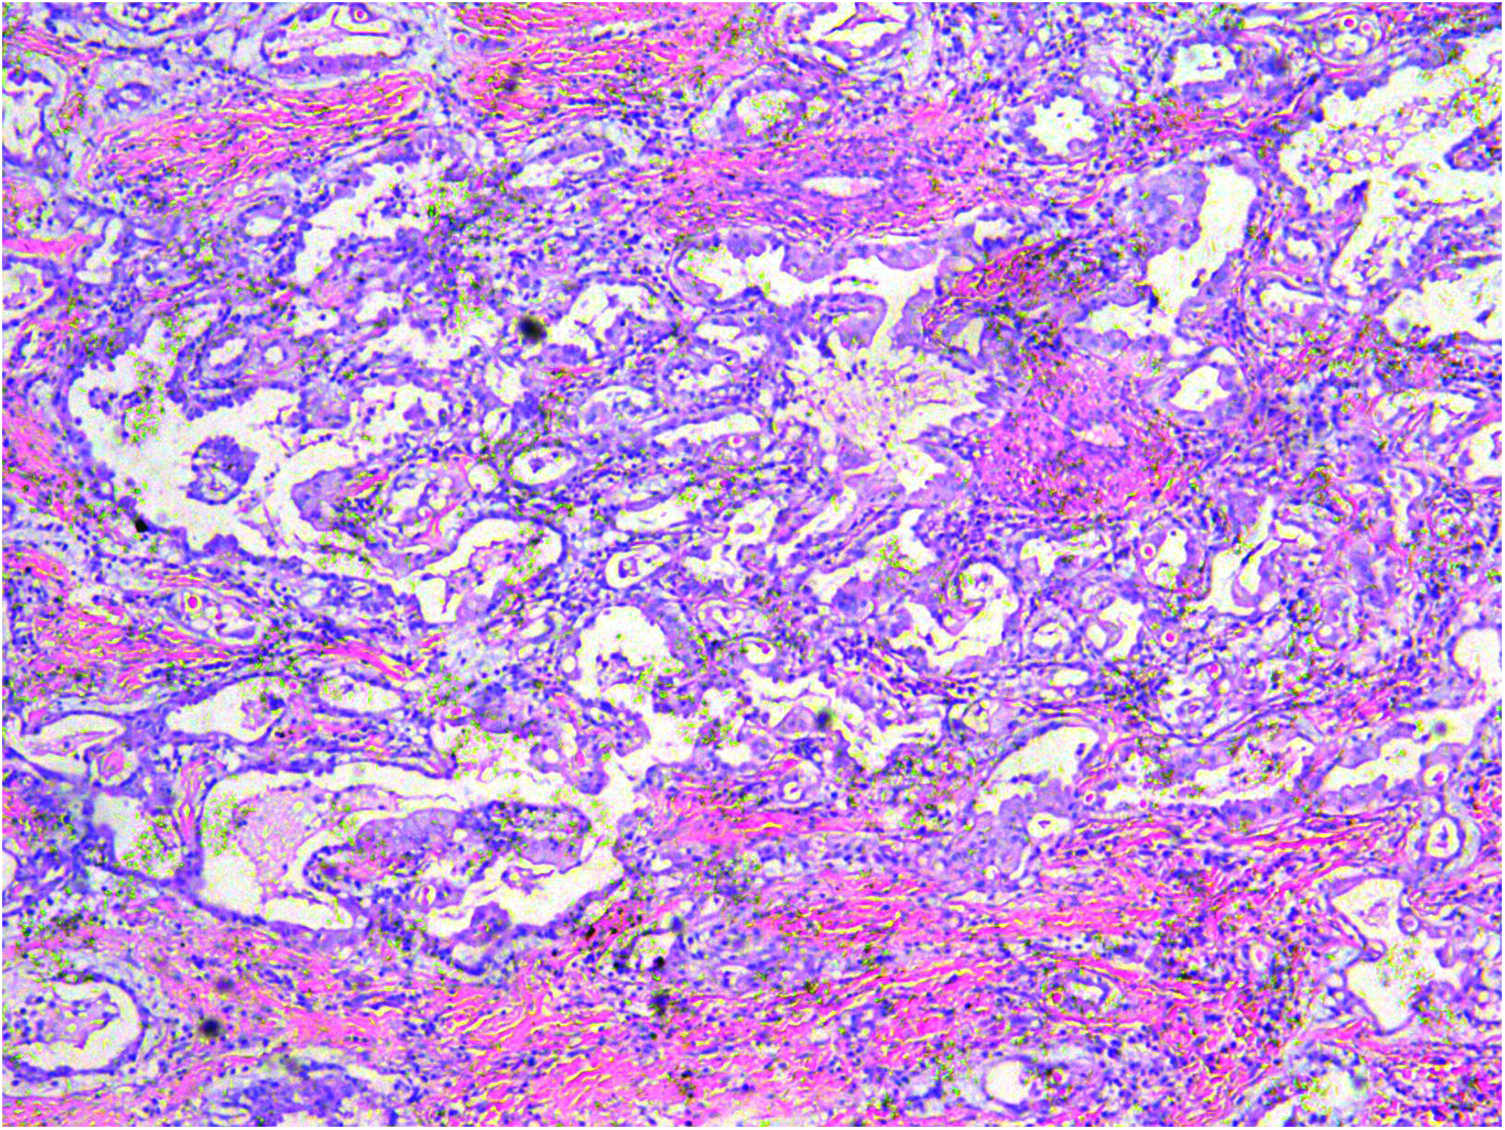

A gross pathological examination indicated a grayish-white, jelly-like mass with a size of 5 cm × 5 cm × 4 cm, and the tip was approximately 5 mm. No envelope was seen. Microscopic examination identified numerous fissures in the tumor tissue. Glandular ducts and microcystic structures were seen (Figure 2). The tumor stroma and mucosa were fibrous; the cells were epithelioid and either vacuolated or cuboidal. The cytoplasm was acidophilic and abundant; the nucleus was large and deeply stained. The karyoplasmic index was high, and the nucleolus was clearly visible (Figure 3). Immunohistochemistry showed calretinin (Figure 4), and CK5/6, CK, D2-40, WT-1, and vimentin were positively expressed. TTF-1, napsin A, CEA, CK7, CD31, CD34, and other markers were negative. The percentage of the Ki-67 positive index was approximately 40.

Figure 2

A microcystic or gridded arrangement, similar to adenomatoid tumors, H&E ×100.

The most common morphologic variants of epithelioid mesothelioma are tubular, papillary, solid, and trabecular. Psammoma bodies may appear in any of these variants. Other uncommon variants include micropapillary, adenomatoid (microcystic), clear cell, migratory, metaplastic, small cell, and lymphohistiocytic (8, 9). Generally, epithelioid tumors contain polygonal, vacuolated, ovoid, or cuboidal cells that mimic reactive mesothelial cells and respond to various types of injury. However, a poorly differentiated epithelioid tumor with pathological mitotic signs was seen in our patient (10).

Biphasic MM is characterized by the presence of mixed tumors consisting of epithelioid and sarcomatoid types, with each type constituting at least 10% of the tumors (8). In our patient, we reported an epithelioid malignant MM with vacuolated or cuboidal tumor cells arranged in microcystic or lattice-like patterns, resembling an adenomatoid tumor.